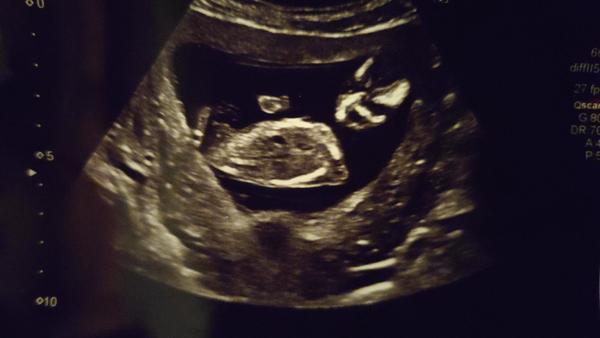

Ahoj holky, tak nastal den D, kdy by se nám to naše malé babby mohlo ukázat. Od rána jsem nervózní a vlastně ani nevím proč a z čeho 😂😂 aby té nervozity nebylo málo, tak už hodinu čekám v čekárně (a to jsem jsem objednaná). Takže jsem ve finále napnutá jak kšandy ještě víc. Závěr tedy je, poslední šance na přihazování sázek a budeme doufat, že se to krásné ukáže. 🙏

Tak vítězna skupina je, ta která tvrdila holcicku.

Paní doktorka neviděla ani kuličky a ani pindíka, ba naopak dle ní viděl krásne pipinu. ♥️♥️